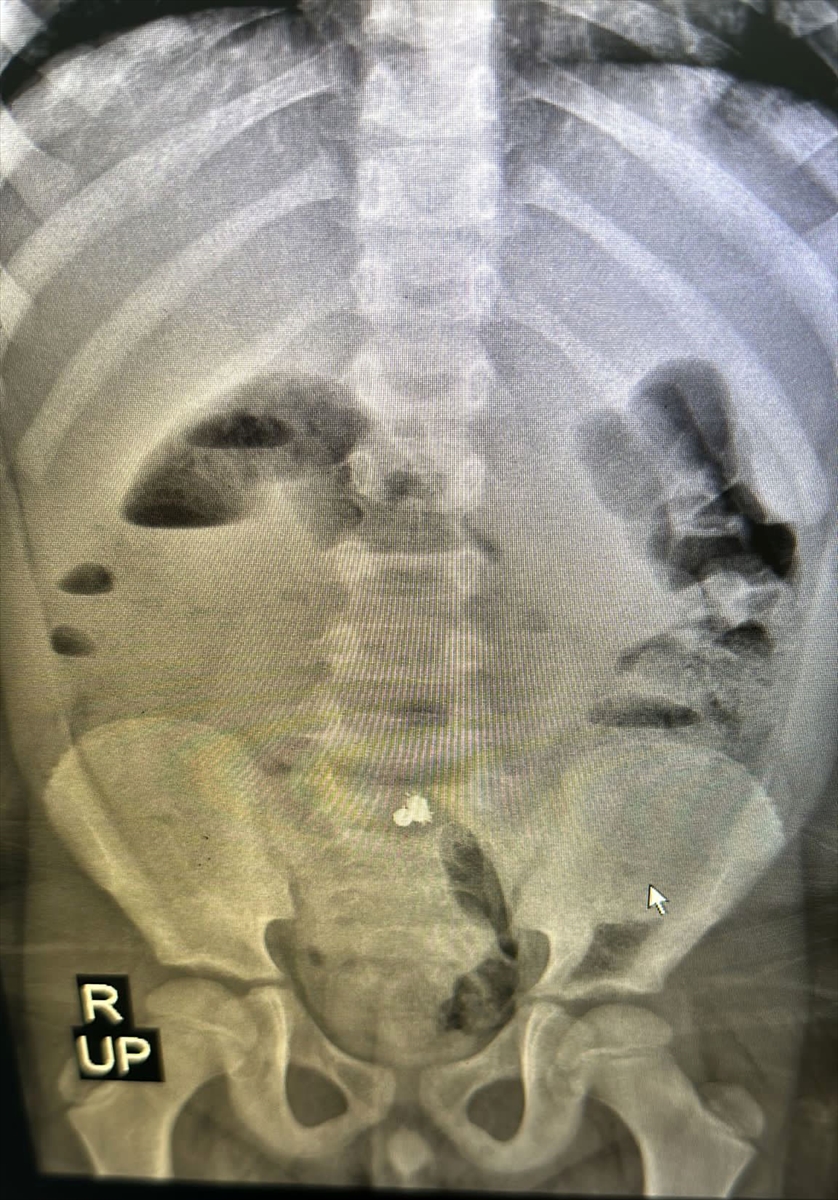

Çekilen röntgende bağırsağına yapışmış 3 parça mıknatıs tespit edilen çocuğun ameliyatına karar verildi.

Cerrahi Tıp Bilimleri Bölümü Çocuk Cerrahisi Anabilim Dalı Dr. Öğr. Üyesi Halil İbrahim Çakmak ve ekibi tarafından gerçekleştirilen operasyonla mıknatıslar çıkarılarak Miraç'ın üç yerden delinen bağırsağı dikildi.